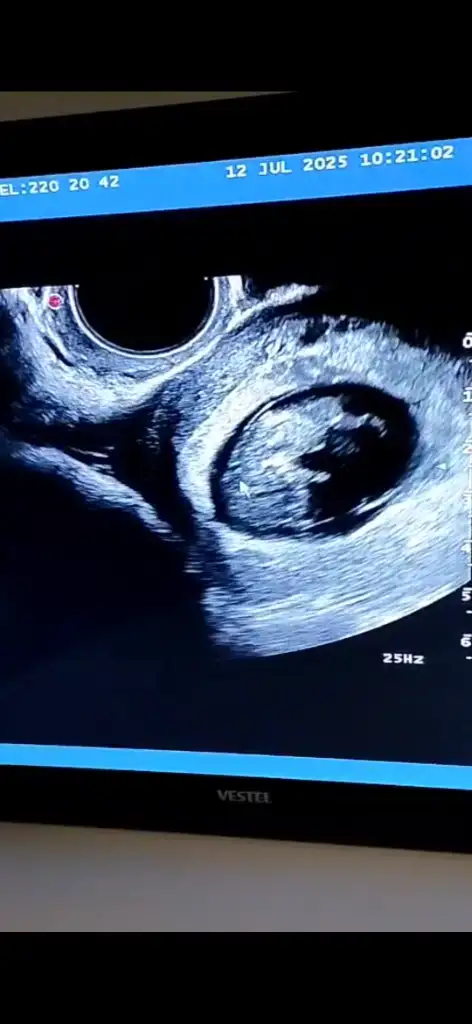

Kızlar bugün doktor kontrolümüz vardı bir hafta sonraya randevu verdi ense kalınlığı ve cinsiyet tahmini için sizce erken değil mi ya da cinsiyet tahmini yapabilecek olan var mı 10+2 :KK68:

Ben bir şey soracağım. Şu uç kısmında 3 uzantı varya. Onlar tam olarak ne :) Doktor bana bacak diye gösterdi ama burda cinsiyet için tahmin ediyorlar🤣 10. haftada bellı olmuyormuş açı. Kız erkek aynı diye okudum ama bilemiyorum😌